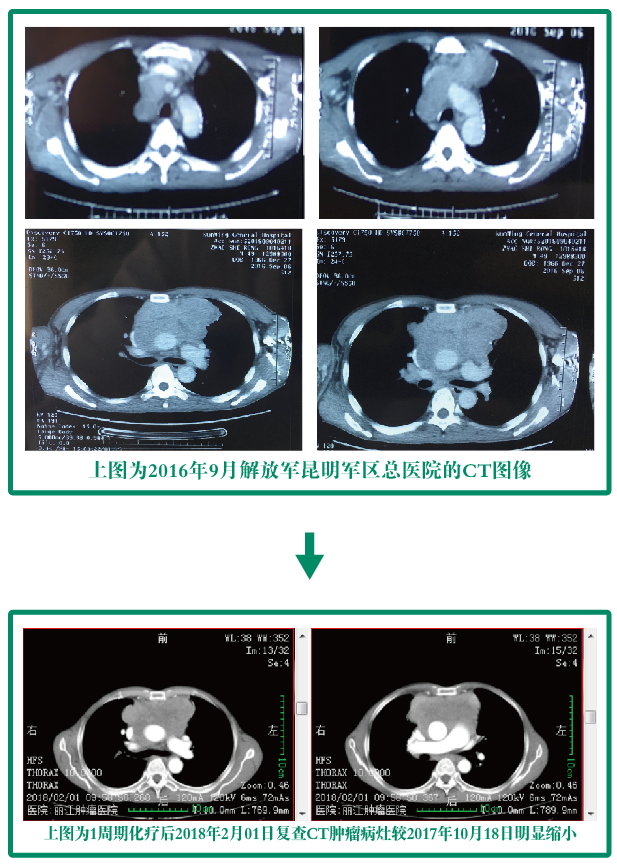

病情摘要:患者自诉于2016年初开始无明显诱因出现胸闷不适、咳嗽,无咳痰,偶有右侧肩甲区疼痛不适,到当地医院就诊行CT检查示:纵膈占位性病变,建议到上级医院就诊。遂昆明军区总医院就诊并于2016-09-08在昆明军区总医院行胸腔镜纵膈肿块活检术,病检示:纵膈中-低化鳞状细胞癌;未行治疗。2017年12月初患者自觉右侧肩甲区疼痛较前明显,伴有右侧上肢疼痛,呈持续性胀痛,并活动后气促,伴有咳嗽,夜间明显,无明显咳痰、胸闷、心悸等不适;于2018年1月6日首次入住我院。入院后于1月13日在我院行1周期“TP”放化疗;化疗结束后于2018年2月01日复查CT示较2017年10月18日外院CT肿瘤病灶明显缩小。

病人治疗CT前后对比图: